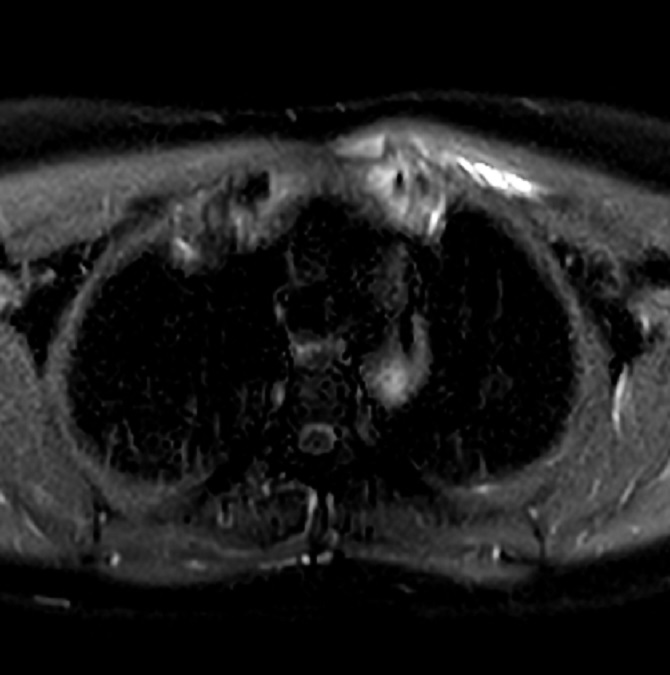

Aspect oedeme de la moelle osseuse

sous-chondral gauche et elargissement de

articulation steno-costale gauche .

Hypovascularisation de zone oedemateuse . |